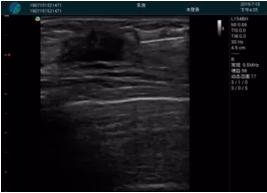

清晰顯示腺體內(nèi)低回聲快影,邊界清晰,包膜較光滑

確定進針路徑并實時監(jiān)測抽吸針與腫塊位置關(guān)系

抽吸針進入腫塊內(nèi)部進行旋切

抽吸過程中可見腫塊明顯縮小,并根據(jù)腫塊位置改變針道位置

抽吸旋切后再進行超聲復(fù)查,原腫塊區(qū)域未見殘留組織及出血

超聲引導(dǎo)下抽吸旋切取出的腫塊組織